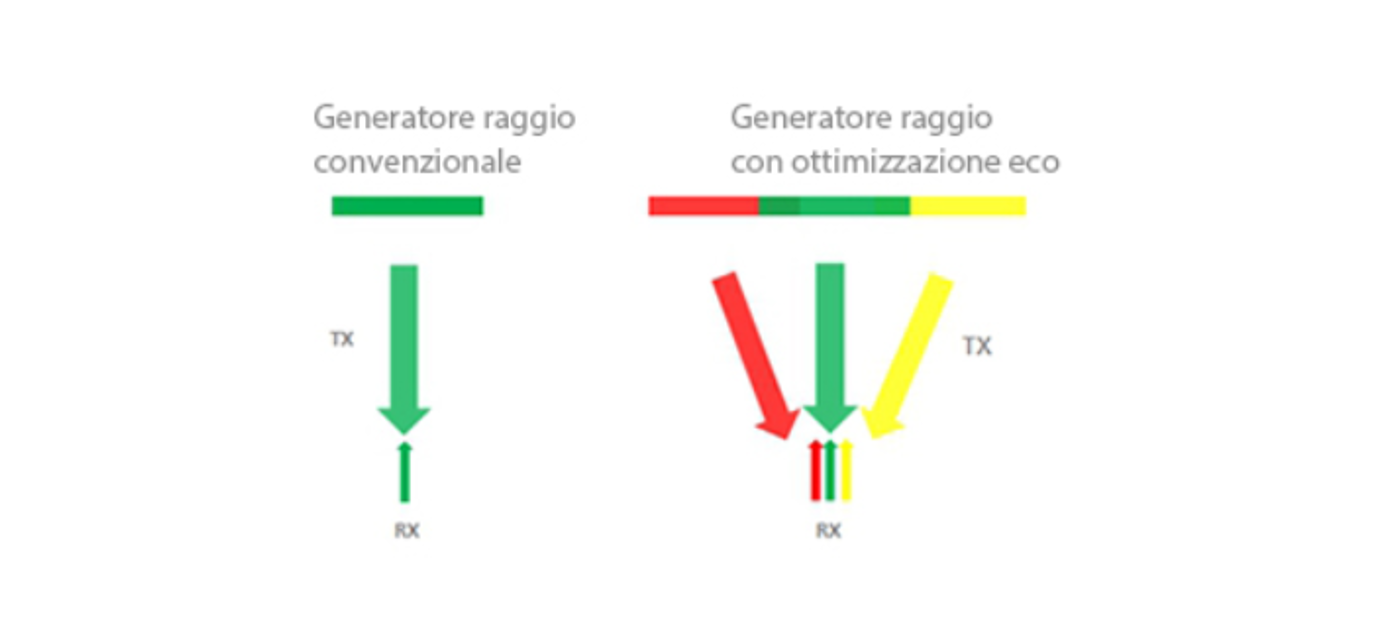

Formazione raggi eco-arricchita

Questa funzione consente l'uso dei segnali eco normalmente trascurati provenienti dai raggi adiacenti, al fine di formare un raggio d'immagine unico, pi├╣ nitido e pi├╣ intenso. Ne consegue una migliore risoluzione grafica "out-of-focus" e una pi├╣ profonda penetrazione nell'immagine.